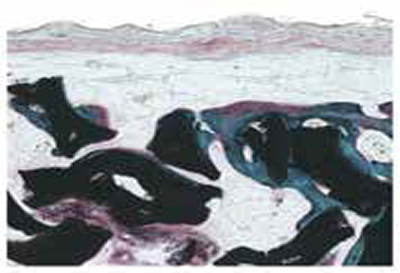

Cross Section

Multi-layer Heterostructure

Rabbit Calvaria Model (Masson's Trichrome)

6 weeks

12 weeks